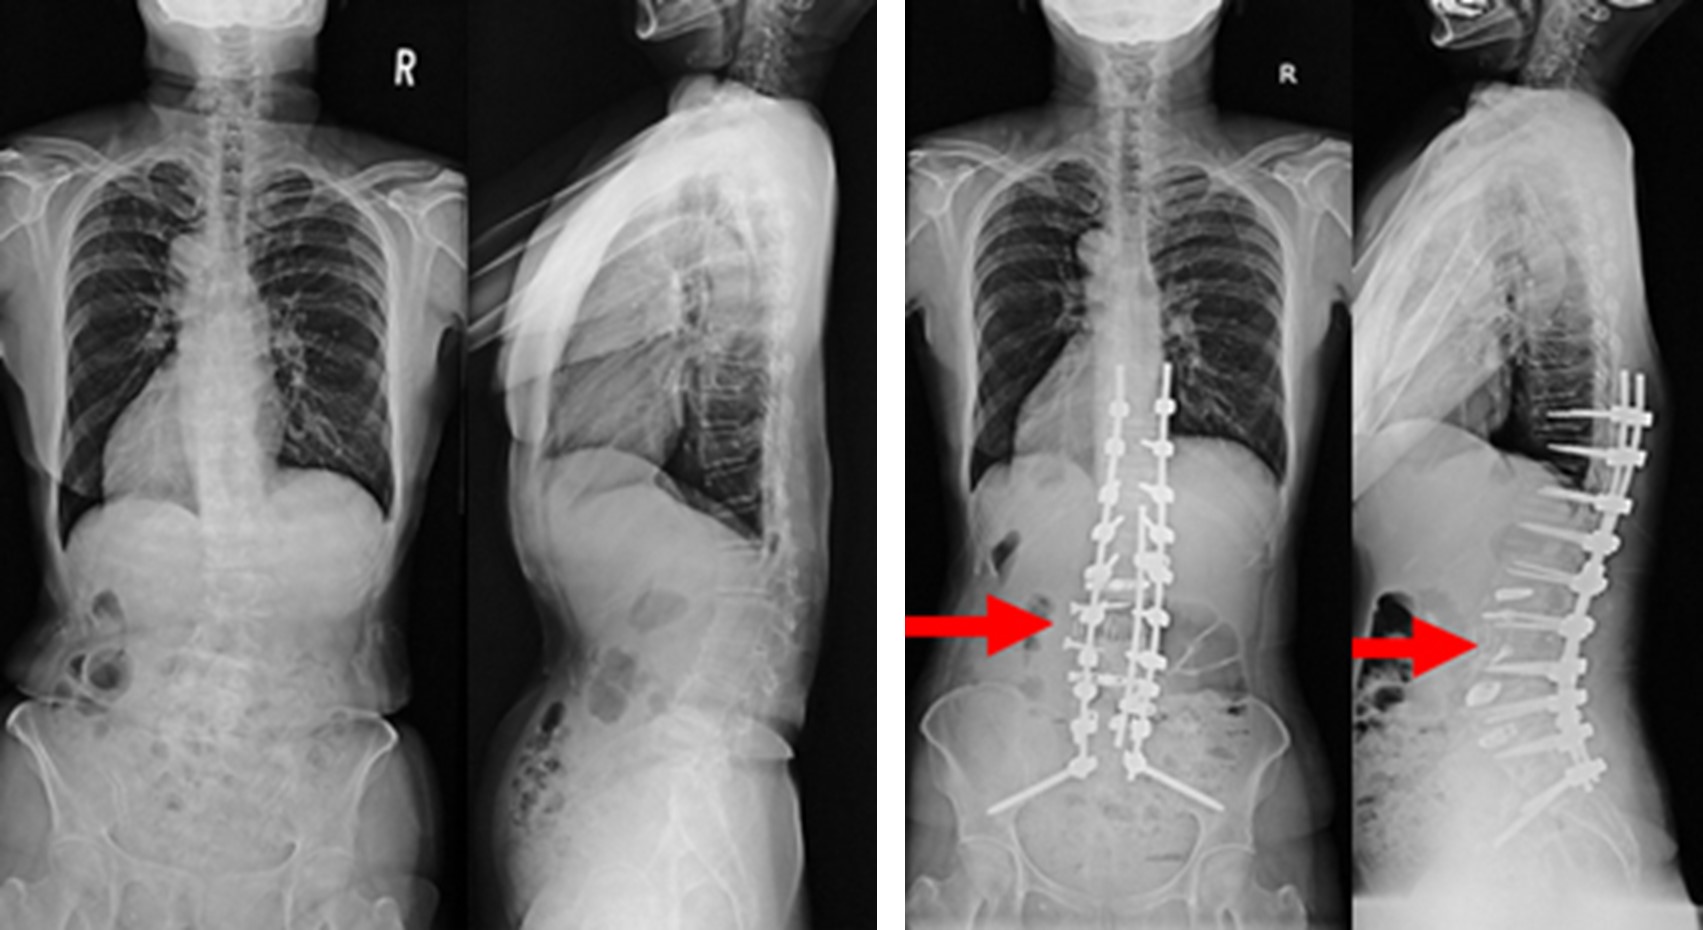

図 (左)術前は腰椎の側弯および強い後弯変形を認め、腰痛により長時間の立位が保持できず、日常生活が著しく制限されていました。

(右)術後は、本来の脊椎の並びに近い形に矯正され、腰痛の改善とともに日常生活レベルの改善を認めました。